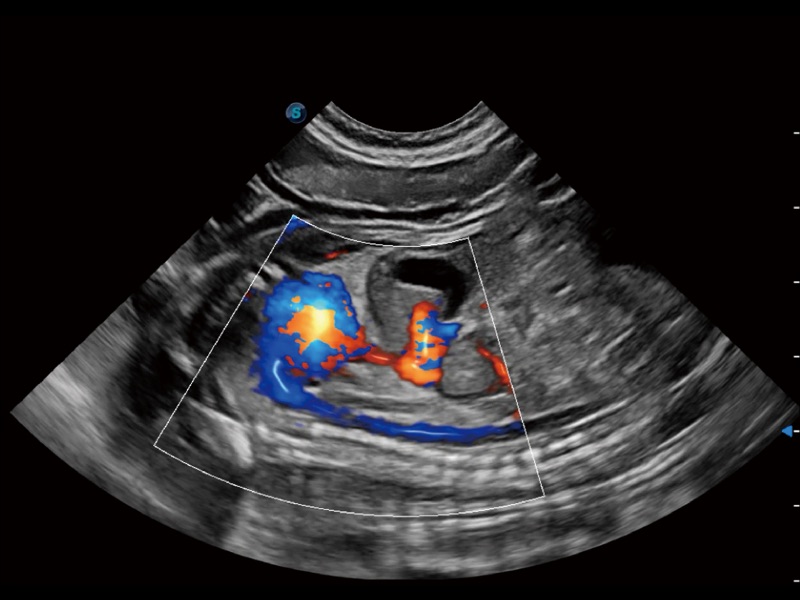

能够基于左心室壁追踪和辛普森法,自动计算射血分数,支持多个可移动点描迹,与手动测量相比,极大节省了动物医生的时间和精力。

通过360度任意调节3条M型取样线,在同一心动周期上观察心脏不同位置的运动曲线,得到准确的心功能测量数据,有效评估心肌运动及左心室功能。

实时用颜色表示心肌组织运动,观察和定量组织的运动情况,对快速检测与评估心肌的灌注和活性、电传导及心肌收缩和舒张功能等均能提供重要的诊断信息。

当心脏测量结果超出正常范围时,可实时预警提示动物医生,减少疾病漏诊概率。